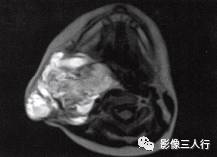

A.B.MRI T1WI显示右侧上颈部大片混杂低信号,其内见蜂窝状更低信号,肌间隙显示不清,并见点、线状高信号。咽、喉、气管受压移位;C〜F.T2WI的横断面、冠状面病变表现为不均匀高信号,形态不规则,可见病变向上、下,向左、右延伸,有“见缝就钻”的特点,气管及周围软组织受压移位

1)若为囊性病灶,T1WI为低信号,T2WI为高信号;囊内合并出血,上层液体为 T1WI显示低信号,T2WI为高信号,下层液体T1WI显示等信号,T2WI为稍高信号。

2)MRI在冠状面、矢状面可显示病灶向上下、左右浸润的范围,具有“见缝就钻”的特点。

3.T2WI病变表现为不均匀的高信号,形态不规则,其内可见分隔,具有“见缝就钻”的特点。气管及周围软组织受压移位。